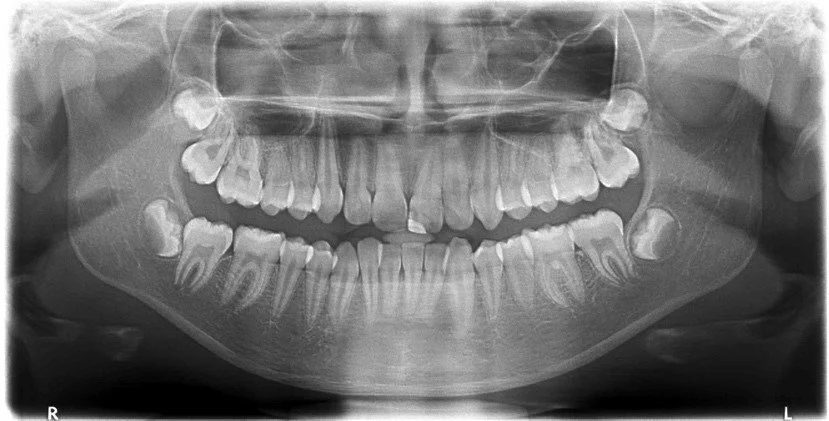

OPG stands for Orthopantomogram (but is more commonly known as a panoramic X-ray). It’s a two-dimensional (2D) panoramic X-ray that captures the entire upper and lower jaws, all teeth, and surrounding jawbone in a single image. At tooth, our scanning centre offers OPGs (panoramic X-rays) as one of our foundational imaging tools.

An OPG gives a Dentist a broad overview of your dental anatomy: tooth positions, jaw relationships, wisdom teeth, bone levels, and potentially any abnormalities or pathology. It’s quick, non-invasive, and uses a relatively low dose of radiation compared to more advanced scans.

An OPG (Panoramic X Ray)